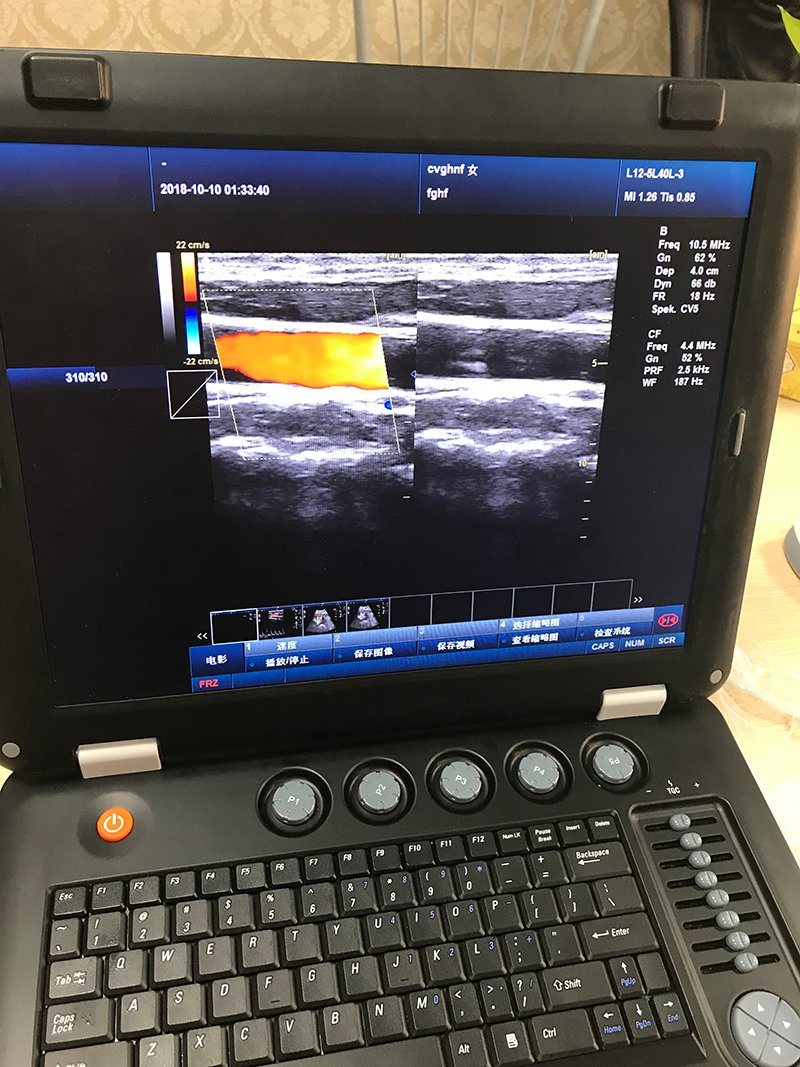

Imaging Modes

B, 2B, 4B, M, B/M, B/C, B/D, B/C/D, B/CFM/D, PDI Color, Dual Color,

2D 3D 4DColor Compound, PW, CW, Duplex/Triplex, CFM, CDE, Directional PD, CD